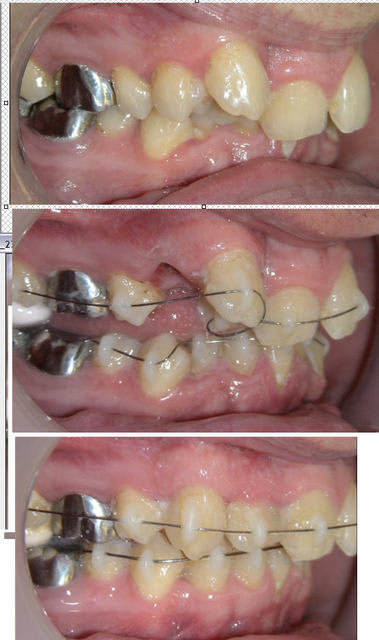

La différence essentielle du système « Danchamon » par rapport à l’ « Incognito » que tu as actuellement dans la bouche repose sur le fait qu’il est infiniment plus simple, réalisé directement au fauteuil sans empreinte ni travail de laboratoire et à un coût qui le met à la portée de toutes les bourses. Certes comme tu peux le voir il n’est pas totalement invisible mais quand même suffisamment discret pour que les patients adultes en soient tous satisfaits. Il est très bien supporté et n’entraîne aucune gêne.

Avec ce système, les dents se déplacent rapidement, avec une facilité déconcertante. Cela correspond au concept d’autokinésis, qui est la propriété d’une dent à se déplacer spontanément dans les trois directions de l’espace.

Ci-dessous, cas d’adulte en 7 mois de traitement. Le fil supérieur n’a même pas été changé, la 12 qui était complètement bloquée en palatin par la 11 et la 13 s'est vestibulée spontanément et l’espace de 14 s’est fermé tout seul… Le traitement n'est pas terminé bien entendu, mais il a quand même progressé d'une manière satisfaisante et avec des moyens plutôt légers.

P.S. : l'exemple que je donne en photo est destiné juste à montrer comment des dents peuvent s'aligner avec les danchamons, ce n'est pas un plan de traitement qui te serait destiné. Faire comme cela pour toi serait d'une stupidité sans borne. C'est évident mais je préfère quand même le préciser.